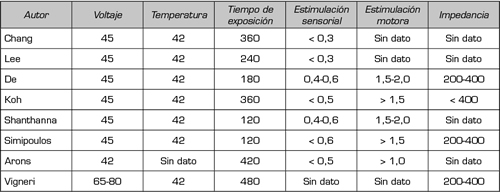

Existen todavía muchas preguntas por responder acerca de los distintos aspectos del conocimiento básico de esta técnica, que pueden tener un impacto importante en los resultados obtenidos de su aplicación clínica. Como ejemplo, quedan por determinar aspectos como la localización del tratamiento, el timming y los parámetros óptimos de la RFP. En cuanto al primer punto, queda por establecer si la aplicación de RF sobre un solo GRD es suficiente para lograr un resultado satisfactorio o si, por lo contrario, dada la distribución divergente de los aferentes nociceptivos a lo largo de varias metámeras adyacentes, es necesario aplicar la RFP a varios ganglios de la raíz dorsal de segmentos vecinos. Con respecto al timming, parecería claro que los efectos modulatorios hasta ahora descritos son temporales, quedando por establecer hasta el momento el valor de repetir los procedimientos, teniendo en cuenta que las alteraciones fisiopatológicas del dolor radicular crónico se mantienen en el tiempo. Por último, es interesante explorar si modificar los parámetros de la radiofrecuencia pulsada (como voltaje, frecuencia y duración del tratamiento), seleccionados hasta ahora en forma empírica, puede repercutir en mejores resultados. Si bien parecería razonable mantener en 42 grados la temperatura de la punta del electrodo, ya que es la base de la seguridad en la utilización de la técnica, el tiempo de exposición y la modificación del voltaje podrían ser los parámetros a modificar. El tiempo de exposición es el factor más frecuentemente modificado (2,3). La mayor parte de los estudios utilizan uno o más ciclos de 120 segundos de duración, dado que se considera esta como segura, en cuanto a la lesión producida en los tejidos. Así, hay trabajos donde utilizan 180, 240, 360 y 480 segundos de duración total (2,3). En nuestro servicio está actualmente en curso un estudio clínico randomizado y doble ciego de pacientes con dolor lumbar radicular unilateral, comparando la eficacia analgésica de las RFP durante 240 y 480 segundos, administrados en dos pulsos.

Otros autores, como Vigneri, proponen aumentar el voltaje entre 65 y 80 voltios, con la finalidad de aumentar la eficacia de la técnica conservando el perfil de seguridad de la radiofrecuencia pulsada (22,23).

En la presente búsqueda bibliográfica se encontraron ocho estudios prospectivos randomizados (23,26-32), y nueve de diseño cuasiexperimental (33-41), de tipo antes y después, evaluando la eficacia de la RF del GRD. Es de destacar que, en los primeros, existe una alta heterogenicidad clínica en relación con el grupo control utilizado como comparador, así como a otras intervenciones utilizadas antes y después del procedimiento evaluado (por ejemplo, esteroides o anestésicos locales epidurales) (Tabla I). Esta heterogenicidad complica la interpretación de los resultados e impide la adecuada realización de un metanálisis (3). La Tabla II muestra los parámetros utilizados en la aplicación de radiofrecuencia pulsada, en los ocho estudios prospectivos randomizados.

Tabla II. Parámetros utilizados en el tratamiento de Radiofrecuencia Pulsada del Ganglio de la Raíz Dorsal en los OCHO estudios randomizados analizados